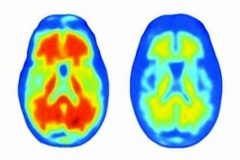

美國阿爾茨海默病新藥仍存疑-

美國阿爾茨海默病新藥仍存疑-

近日,由美國生物技術(shù)公司百健研發(fā)的β—淀粉樣蛋白抗體aducanumab(市場名為Aduhelm),成為自2003年以來美國批準(zhǔn)的第一個(gè)阿爾茨海默病新藥物。